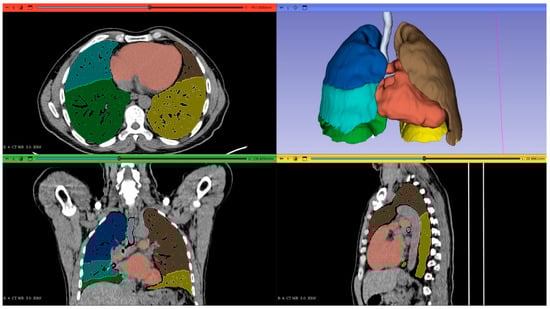

1. Introduction

2.2. Computed Tomography Image Acquisition and Postprocessing